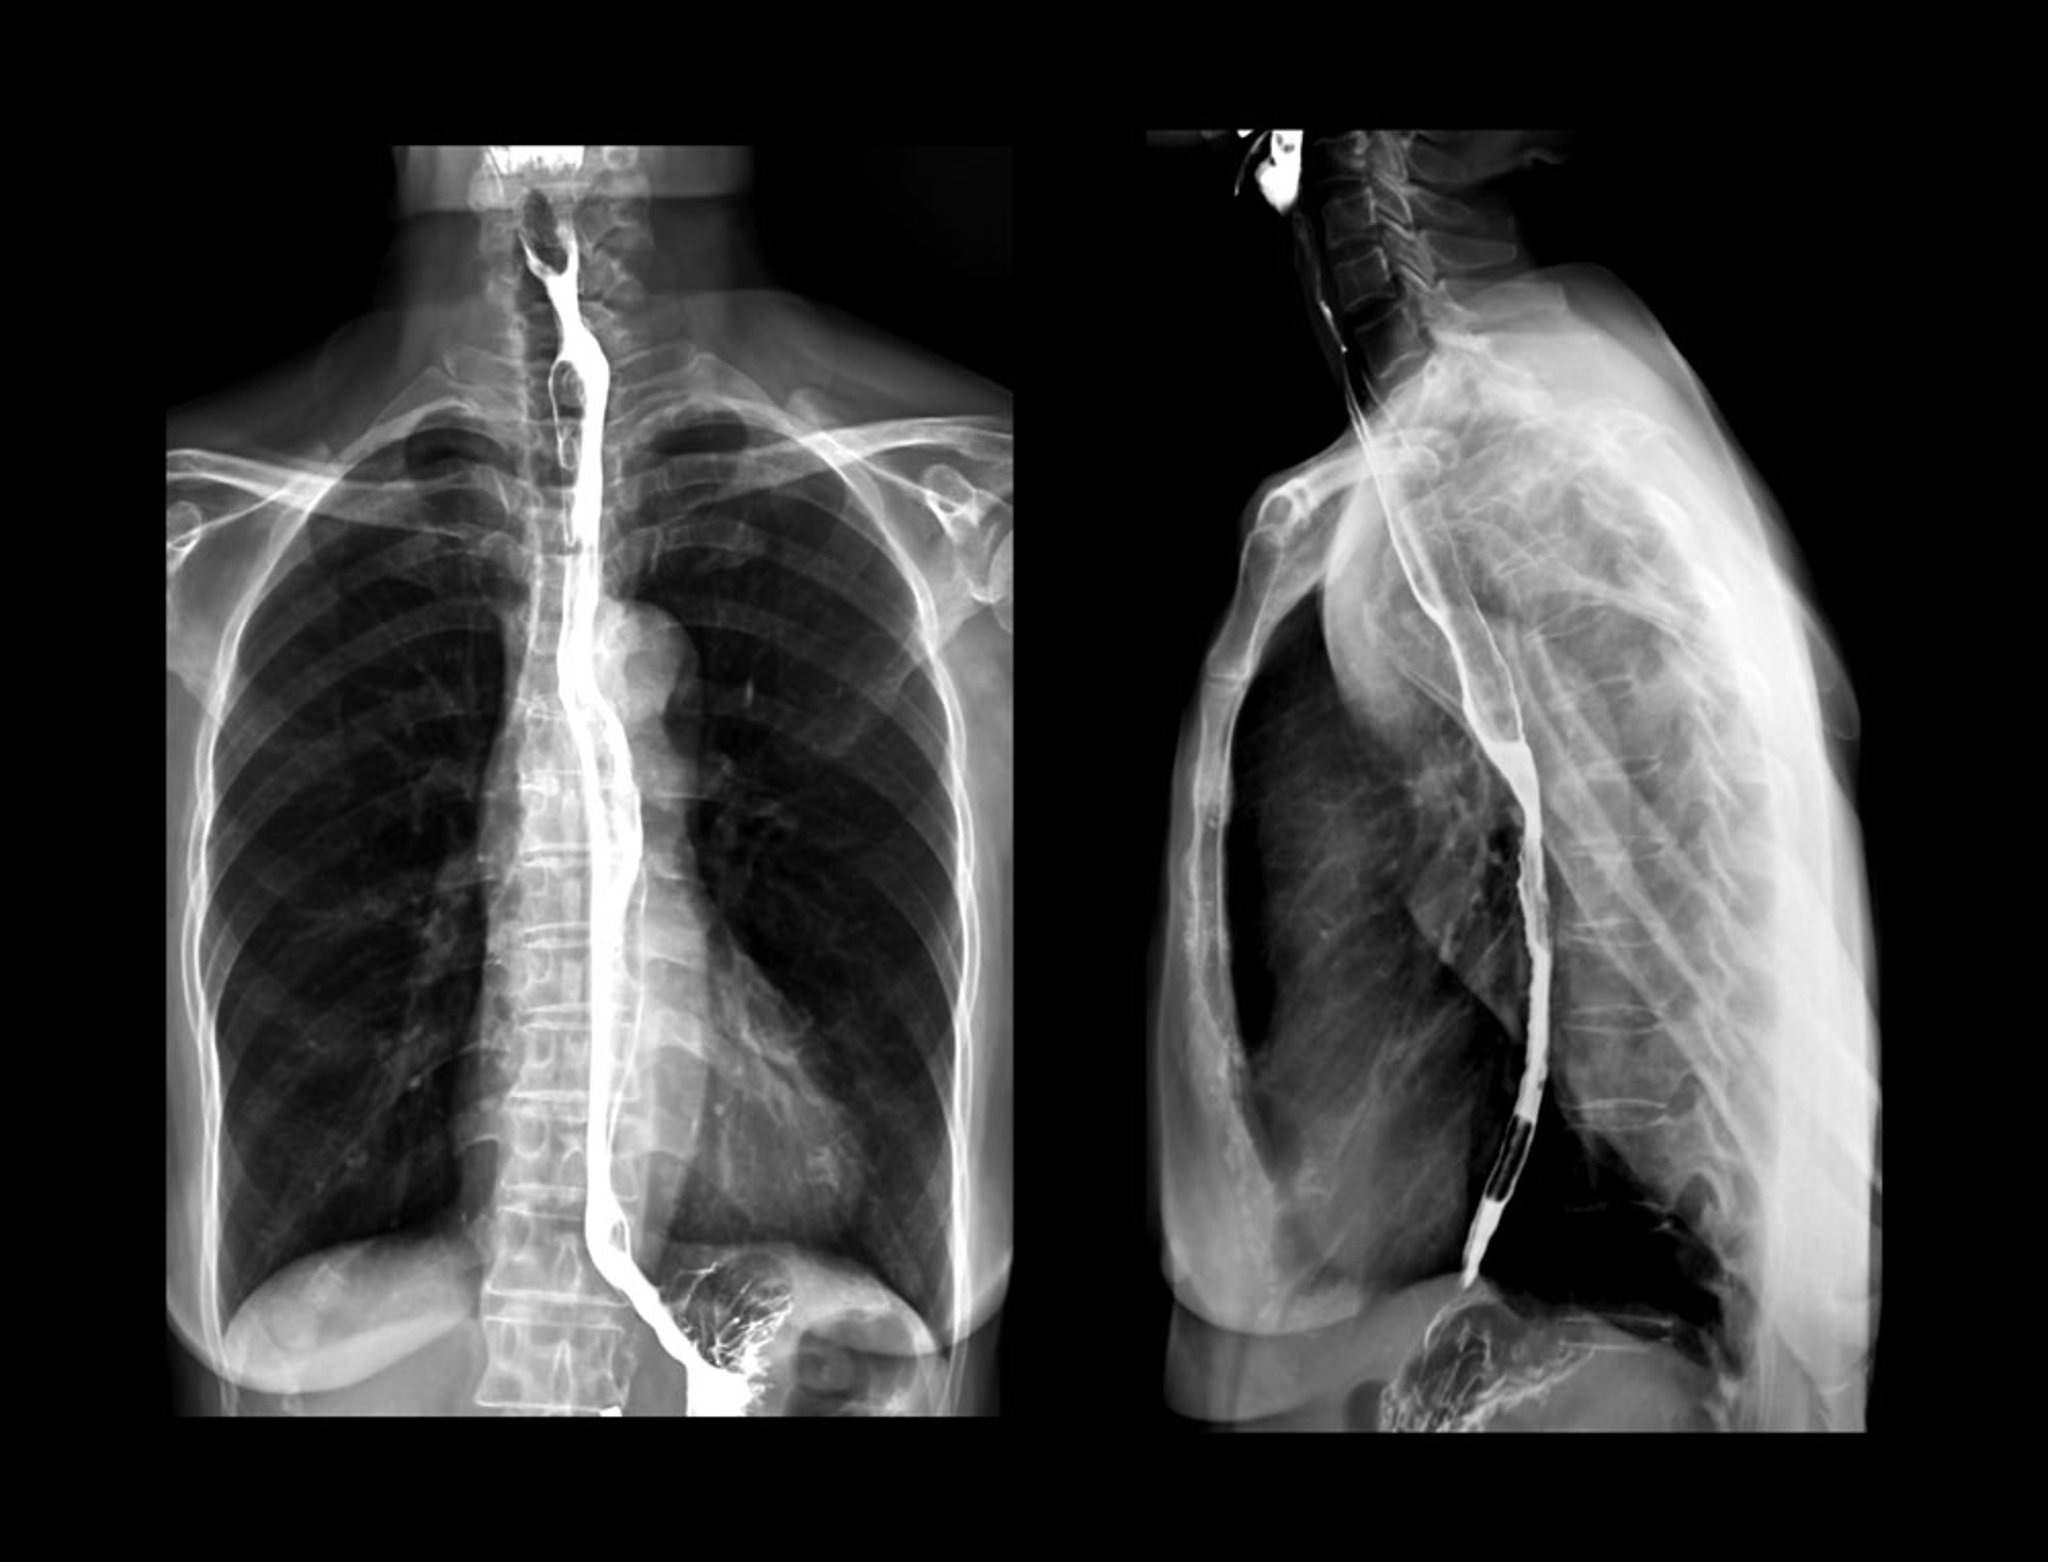

Barium Swallow X-Rays

For a barium swallow test, people are given barium in a liquid to drink before x-rays are taken. In these x-rays, the barium is the white liquid that is outlining the esophagus.